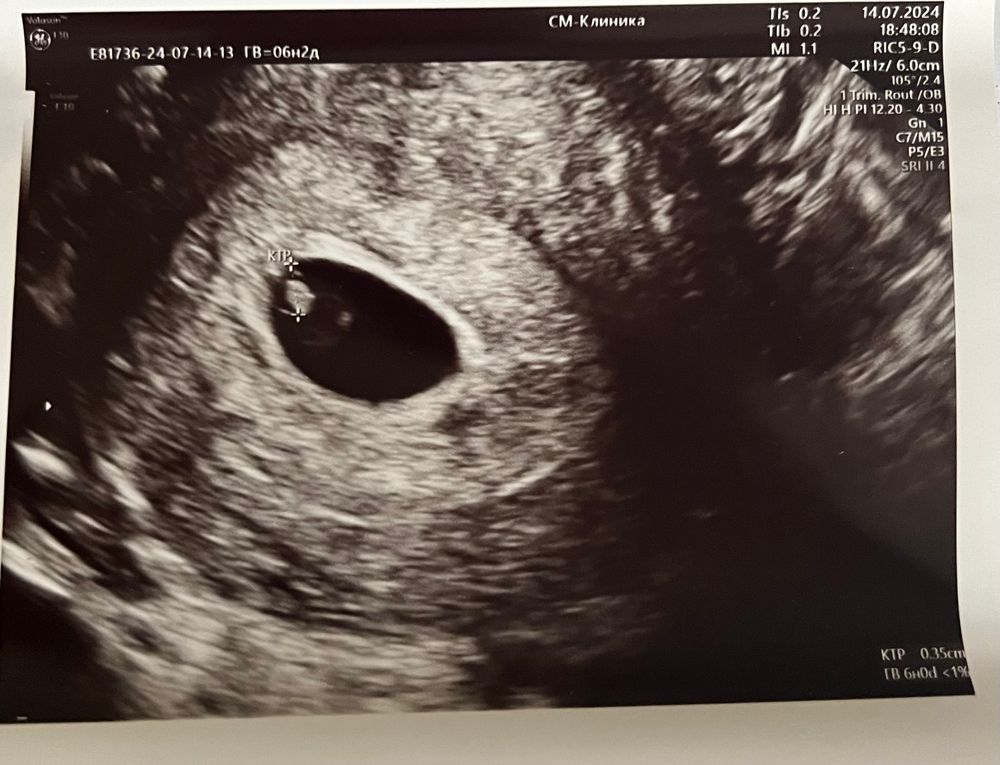

25дпп. Услышали сердечко 🥹🥰

14.07.2024